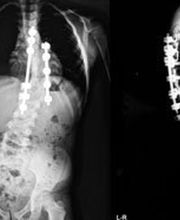

Lo Studio Zizza del Dr. Sebastiano di Catania è specializzato in fisiatria, con particolare attenzione alla diagnosi, terapia e riabilitazione della scoliosi e delle deformità della colonna vertebrale e dellapparato muscolo-scheletrico in età evolutiva. Il Dr. Zizza svolge inoltre visite specialistiche in ortopedia e traumatologia, dedicandosi in modo specifico alle patologie degli arti inferiori e del piede. Lo studio riceve esclusivamente su appuntamento, offrendo un servizio professionale e personalizzato volto alla prevenzione, cura e gestione delle principali problematiche ortopediche e posturali dellinfanzia e delladolescenza.